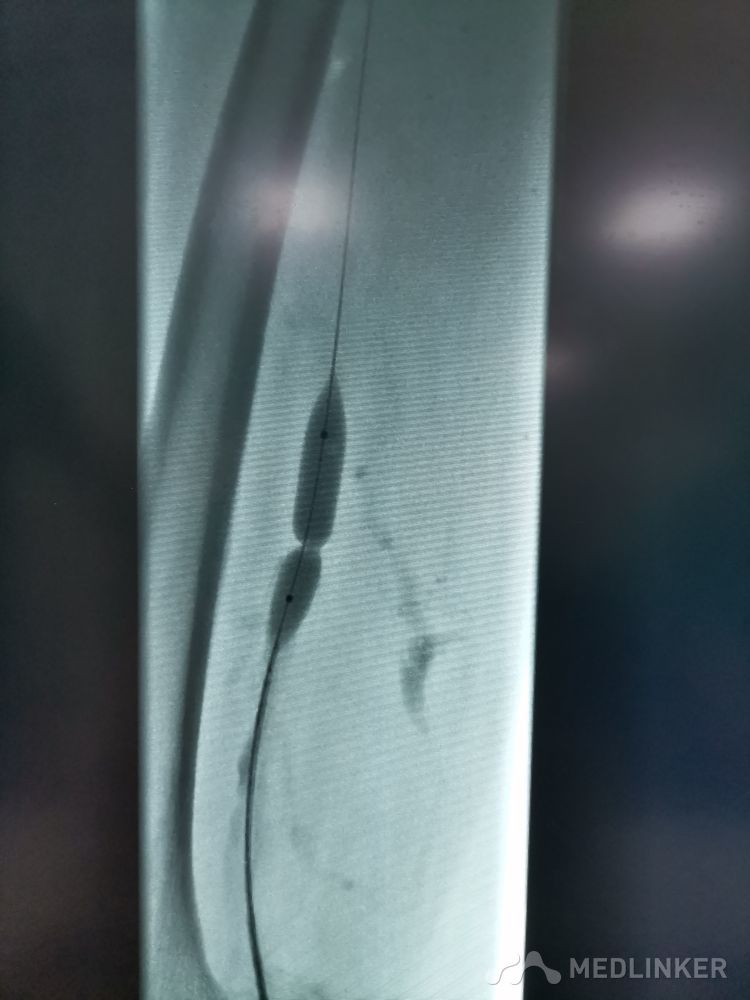

重视髂静脉压迫综合征。不同的临床表现,相同的病因,均为髂静脉压迫所致。第一例,表现为下肢静脉曲张伴溃疡,造影证实,髂静脉支架置入后解决。第二例,表现为左侧髂股静脉血栓,置管溶栓并髂静脉支架置入开通血管。第三例,下肢深静脉血栓后遗症,外院已行髂静脉支架置入,但皮肤营养情况仍持续加重,开通股浅 ,可见病变局部异常坚硬。精准施治,对症下药。